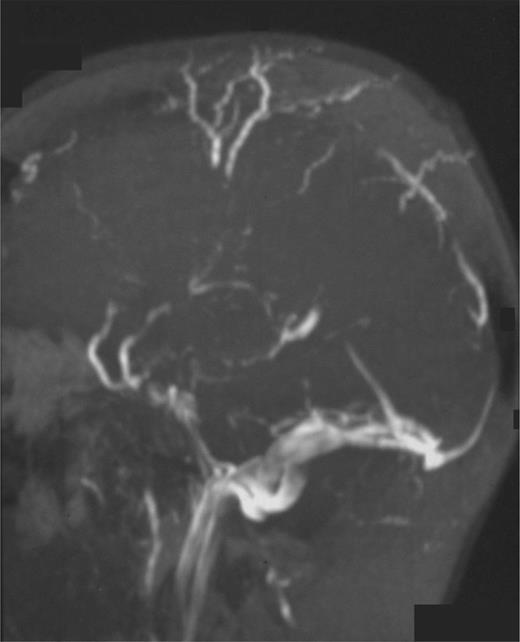

Superior sagittal sinus thrombosis (Figure 1) is the most frequent neurologic complication and results in death in more than one-third of cases.34 There is also a greater tendency for hemorrhagic infarction after this complication. Thromboses in the sagittal sinus, lateral sinus, cavernous sinus, and sigmoid sinus may all result in neurologic symptoms and signs such as severe headache, vomiting, seizures, altered level of consciousness, papilloedema, VI and VII cranial nerve palsies, central retinal vein thrombosis, and cerebellar or lower cranial nerve signs for sigmoid sinus thrombosis.35 Because the mortality rate from cerebrovascular events remains high, prompt diagnosis (frequently requiring sophisticated imaging techniques such as magnetic resonance imaging, magnetic resonance angiography, or magnetic resonance venography) and a high clinical suspicion is required. Magnetic resonance imaging techniques are preferred because contrast agents used with classic angiography could provoke exacerbation of hemolysis or nephrotoxicity.

Magnetic resonance angiography in a patient with PNH and superior sagittal sinus thrombosis with collateral vessel formation.